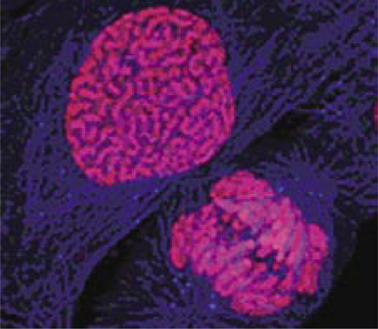

Scientists have unlocked the entire genetic code of two of the most common cancers – skin and lung – a move they say could revolutionise cancer care.

It could even be possible to develop MoT-style blood tests for healthy adults that can check for tell-tale DNA patterns suggestive of cancer. The scientists found the DNA code for a skin cancer called melanoma contained more than 30,000 errors almost entirely caused by too much sun exposure. The lung cancer DNA code had more than 23,000 errors largely triggered by cigarette smoke exposure. From this, the experts estimate a typical smoker acquires one new mutation for every 15 cigarettes they smoke. Although many of these mutations will be harmless, some will trigger cancer.